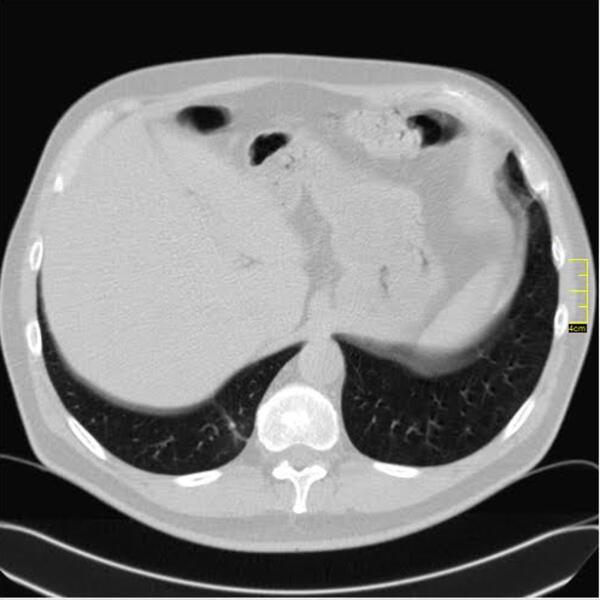

April 2021. Počinju da dolaze pacijenti koji imaju drugačiji nalaz.

Ono što je karakteristično je to da su ovo nalazi koji su 2. i 3. dana bolesti u I fazi. Znači ne u progresivnoj, već u uvodnoj fazi kada uglavnom nema CT znaka. Fibrozne trake već drugog dana???? Ground glass oko većih grana bronha. Kao da bolest ne može da sačeka, kao da klija gde stigne.

Klinička slika se razlikuje od britanskog soja. To se slažu i moji pulmolozi. Za sada je desetak pacijenata (kod mene), malo za zaključke, ali to su pacijenti u kratkom vremenskom periodu od 31.03.2021. godine do 14.04.2021. godine.

Neće mi biti iznenađenje ako se pokaže da već imamo novi soj virusa. Ne mogu da tvrdim da je brazilski, ali se svakako razlikuje.